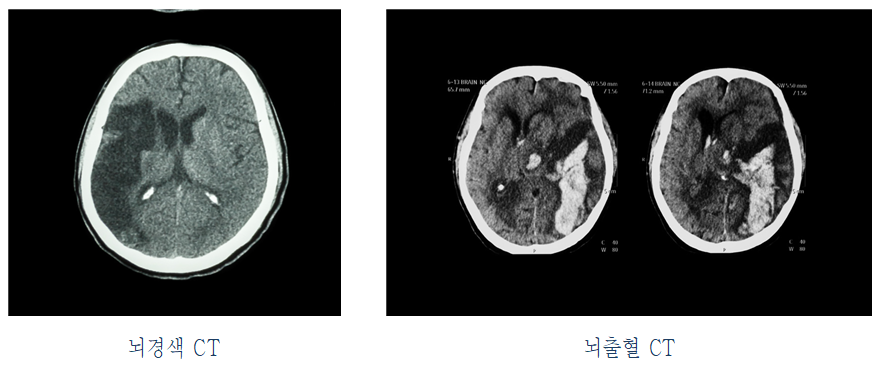

□ 중풍(中風)은 두개 내외 혈관의 파열(뇌출혈), 폐색(뇌경색) 등 다양한 병리학적 변화에 의해 뇌기능의 상실이 나타나는 질환입니다.

□ 중풍 후유증은 이 중풍으로 인해 나타난 증상들이 지속되는 뇌기능 장애 후유증을 말합니다. 뇌출혈이나 뇌경색으로 손상된 뇌 영역과 관련된 신경학적 결손 증상이 편마비, 무감각증, 실어증, 운동 실조증 등의 주증상으로 나타날 수 있습니다.